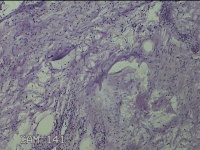

直肠息肉

性别

女

年龄

39岁

临床诊断

混合痔

一般病史

反复肛门肿物3月。

标本名称

大体所见

灰白暗红色条索状肿物5.3x2x0.8cm一个,表面糜烂,切面灰白暗红色,质软。

图1